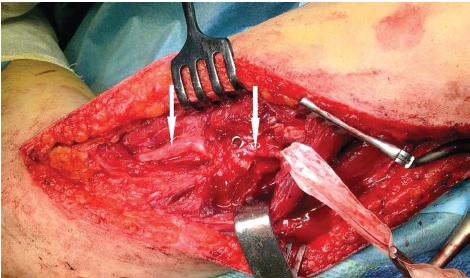

По данным рентгенографии определялся перелом левой плечевой кости на уровне средней трети диафиза после остеосинтеза блокированным штифтом, отсутствие признаков консо- лидации. Штифт на 2 см не доходил до дна костномозгового канала плечевой кости, при этом определялось выстояние верхушки штифта над поверхностью головки плечевой кости на 3 мм. Оба дистальных блокирующих винта проведены в направлении снаружи кнутри (рис. 1).

Рис. 1. Рентгенограммы после остеосинтеза левой плечевой кости штифтом: a — прямая проекция; b — боковая проекция

Fig. 1. X-rays after the left humeral bone nailing: a — anteroposterior view; b — lateral view

В данном случае к повреждению привела совокупность нескольких технических ошибок при выполнении остеосинтеза. Во-первых, был подобран штифт меньшей, чем необходимо, длины. На послеоперационных рентгенограммах видно, что даже с учетом того, что проксимальный конец штифта на несколько миллиметров выстоит над головкой плечевой кости, дефицит длины составляет около 2 см. Во-вторых, несмотря на наличие в штифте отверстия для дистального блокирования в сагиттальном направлении, оба блокирующих винта проведены в направлении снаружи кнутри. С учетом недостаточной длины штифта такое блокирование неизбежно производится в проекции лучевого нерва [9]. При недостаточной защите мягких тканей нервный ствол с высокой вероятностью повреждается при сверлении или введении блокирующего винта. Повреждение режущей кромкой сверла в ряде случаев приводит к полному разрыву нерва, что, очевидно, в данном случае и произошло.